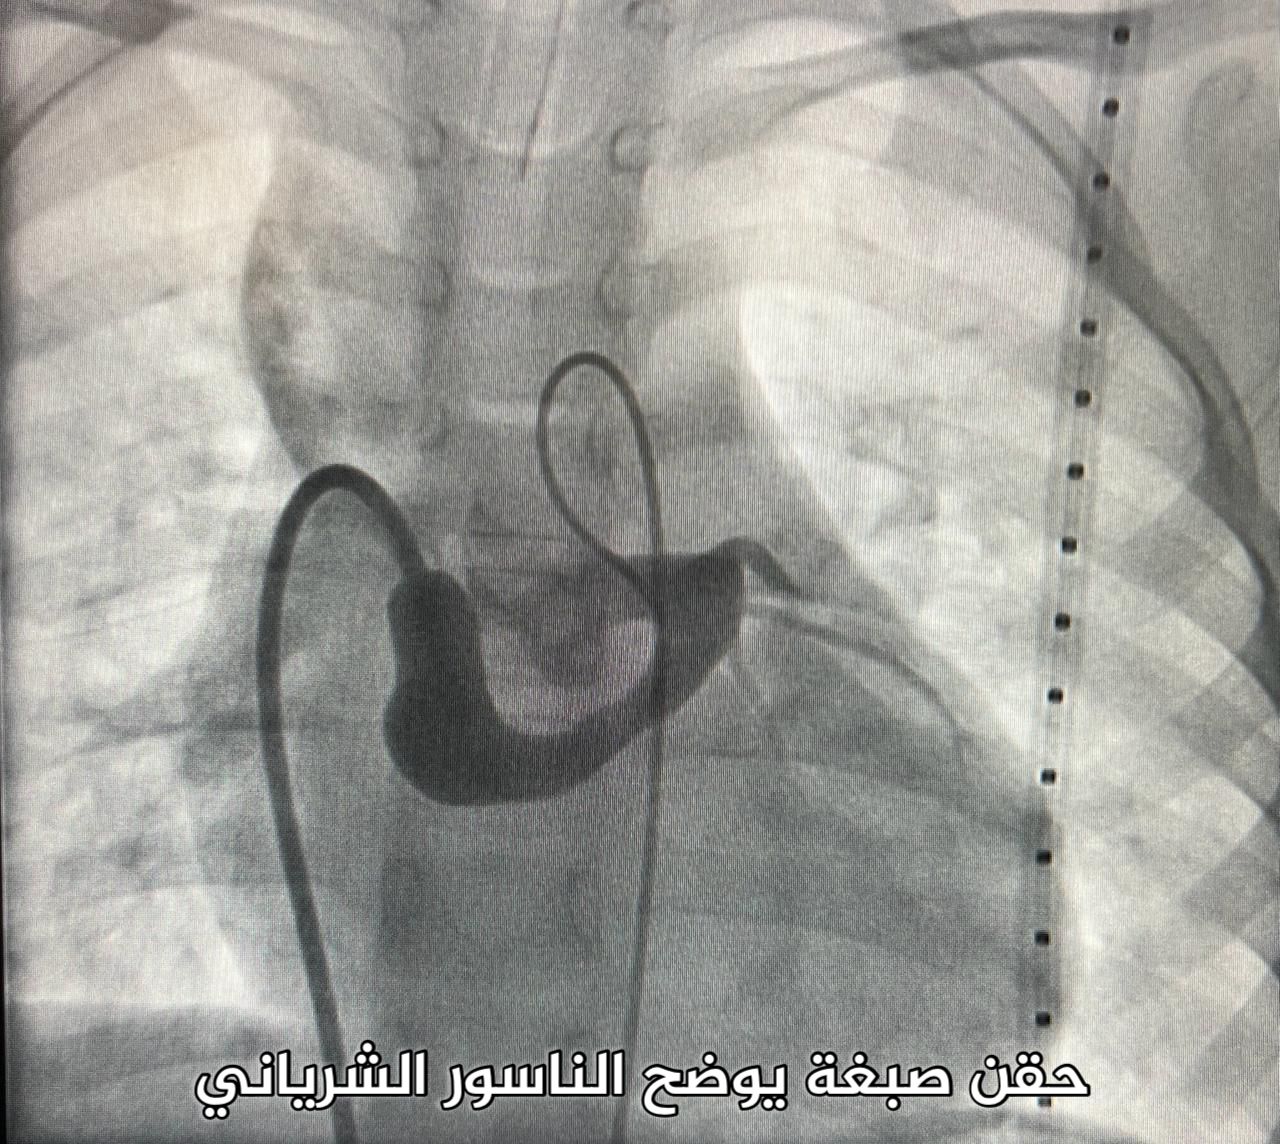

كان يعاني من مشكلة صحية تعرف بالناسور الشرياني، وهي من الحالات النادرة.

وأوضح التجمع أن الفحوصات والتحاليل الطبية التي أُجريت للطفل بينت وجود الناسور في المنطقة الكامنة بين الشريان التاجي الأيسر والأذين الأيمن مما استدعى الفريق المعالج في قسم الأطفال بالمركز للقيام بتدخل طبي عاجل.

وأشار إلى أنه تم إغلاق الناسور الشرياني لمنع حدوث الجلطات الشريانية وفشل عضلة القلب والالتهاب لا سمح الله.

حيث تكللت العملية بالنجاح ولله الحمد في فترة زمنية لم تزد عن ساعة واحدة من خلال إجراء القسطرة الشريانية، وبعد الاطمئنان على الحالة الصحية للطفل غادر المركز مع أسرته مصحوبا بالسلامة والعافية.